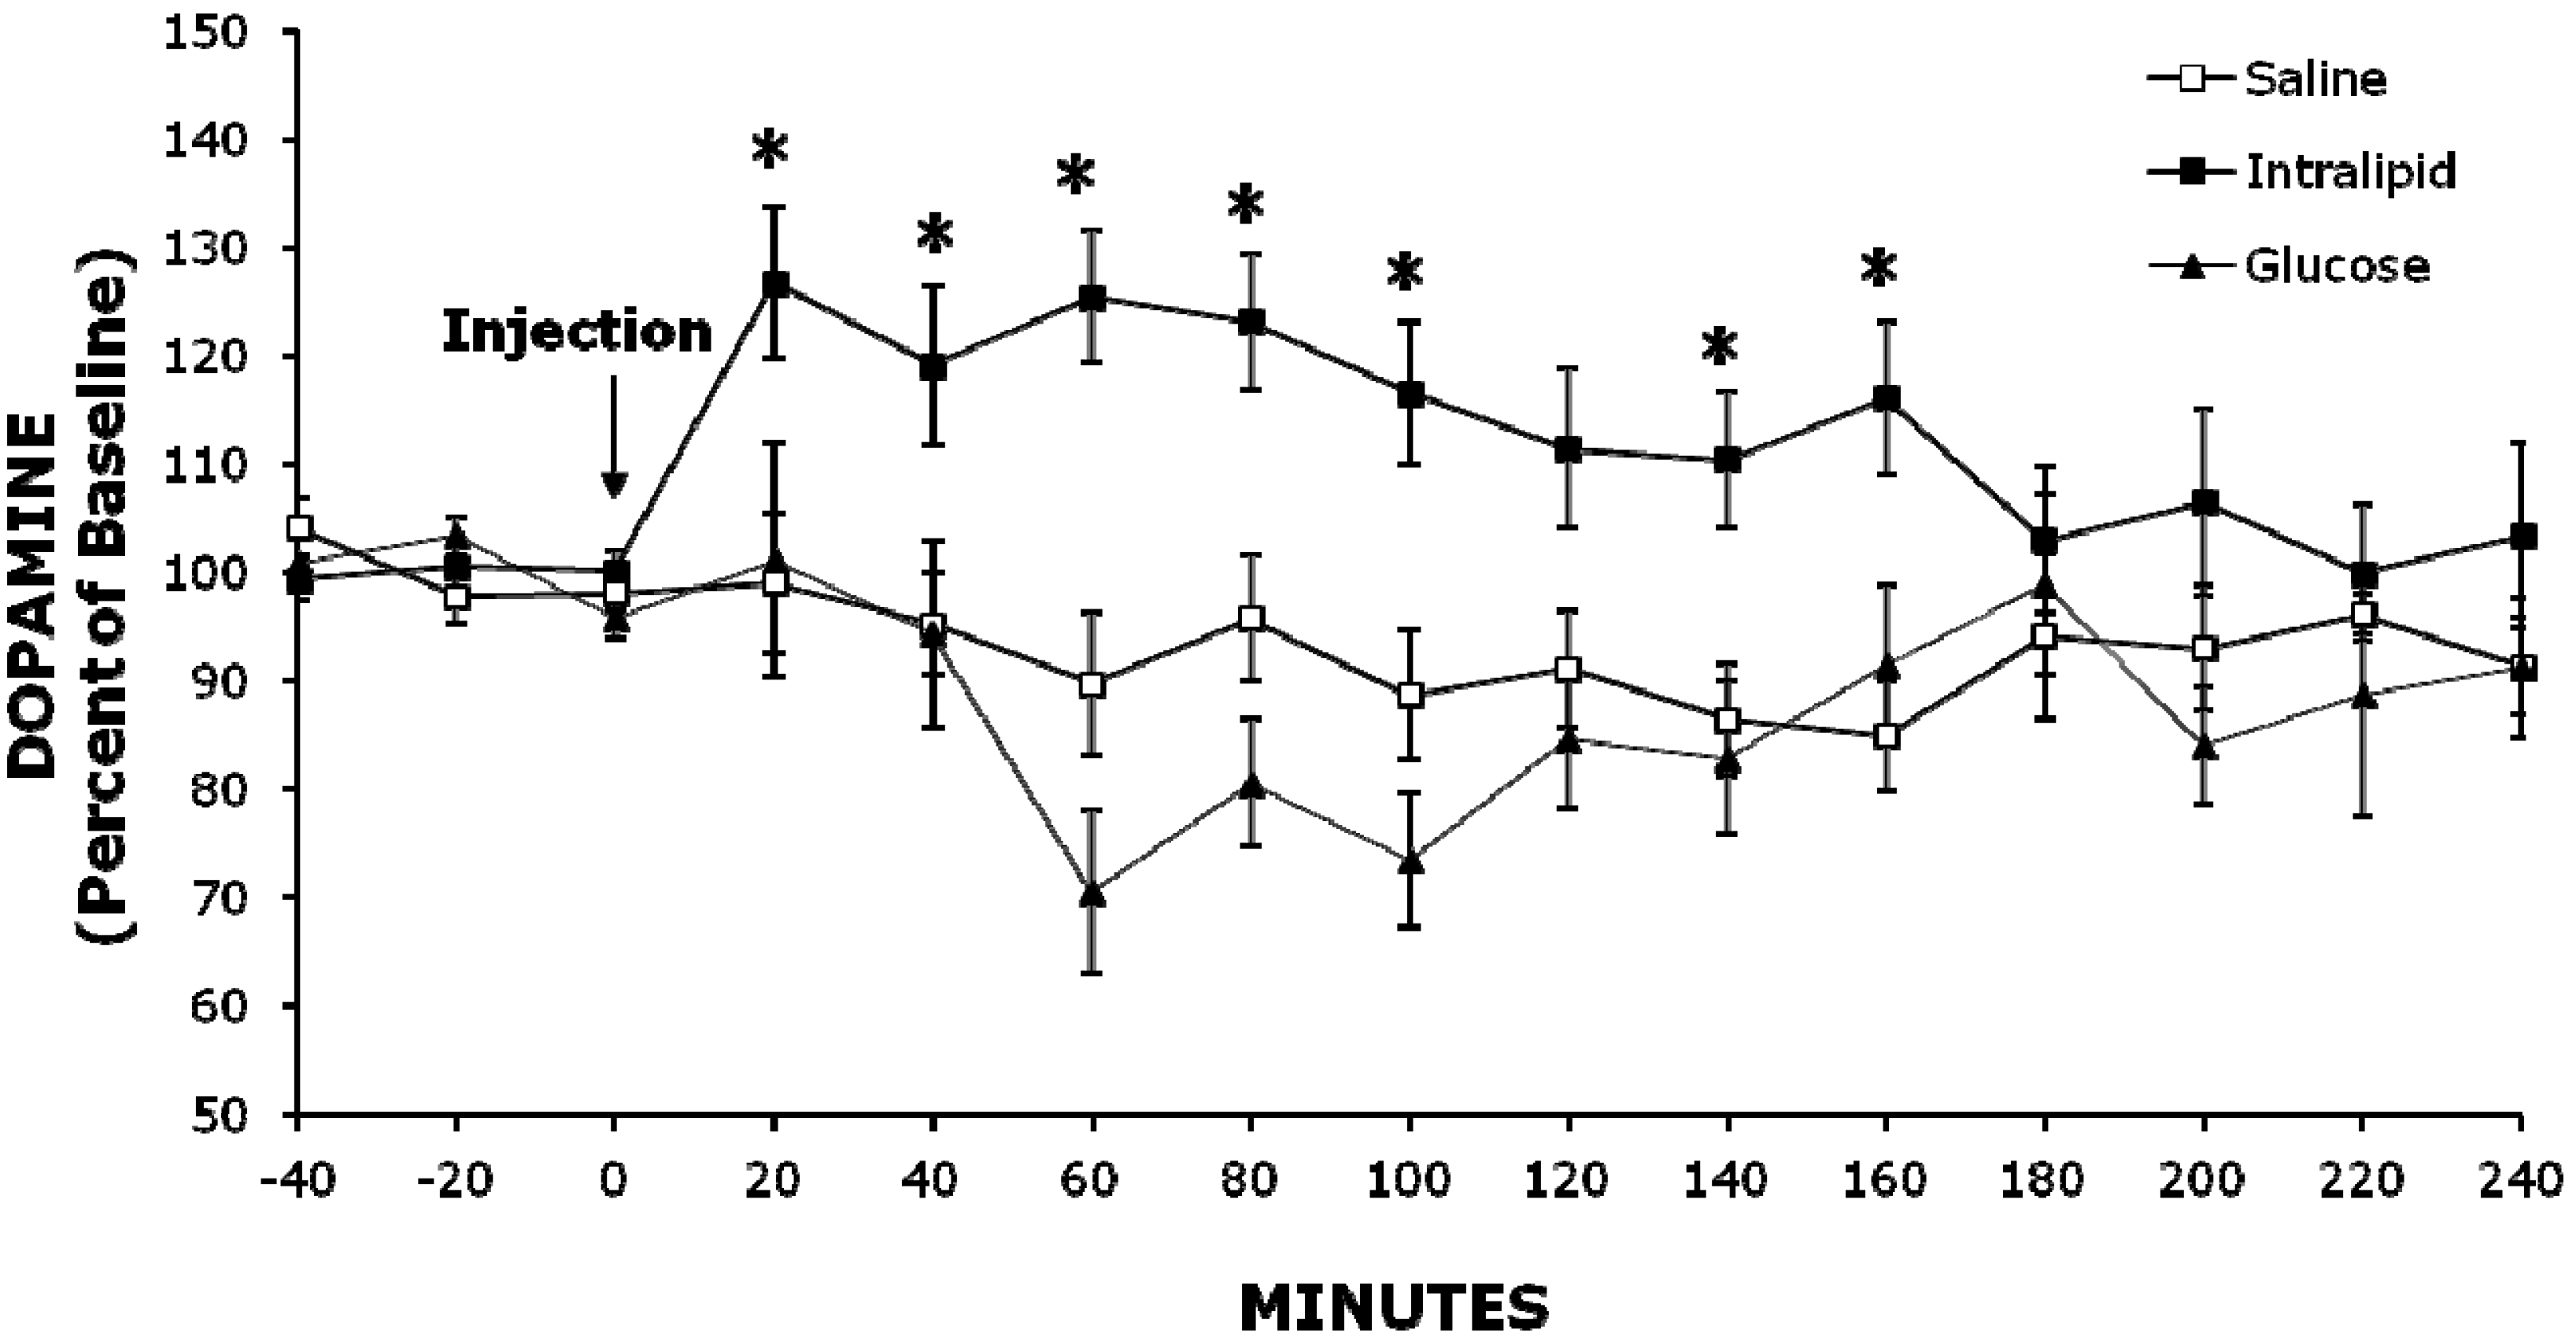

| Experiment 2 | Baseline | 60 min | 120 min | 180 min |

| DOPAC | ||||

| Intralipid | 99 ± 1% | 112 ± 7% | 100 ± 5% | 98 ± 3% |

| Glucose | 97 ± 1% | 93 ± 5% | 86 ± 3% | 82 ± 6% |

| Saline | 101 ± 2% | 94 ± 5% | 108 ± 12% | 103 ± 10% |

| HVA | ||||

| Intralipid | 99 ± 2% | 113 ± 8% | 103 ± 4% | 101 ± 5% |

| Glucose | 98 ± 1% | 95 ± 6% | 90 ± 2% | 92 ± 3% |

| Saline | 98 ± 3% | 97 ± 6% | 105 ± 8% | 103 ± 7% |

2.2. Experiment 2: Injection of Intralipid Increases Extracellular NAc DA Levels Compared to Glucose or Saline